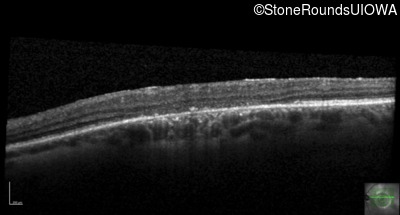

Optical Coherence Tomography - Left - 10/160 sc

Exemplar / OCT Stack